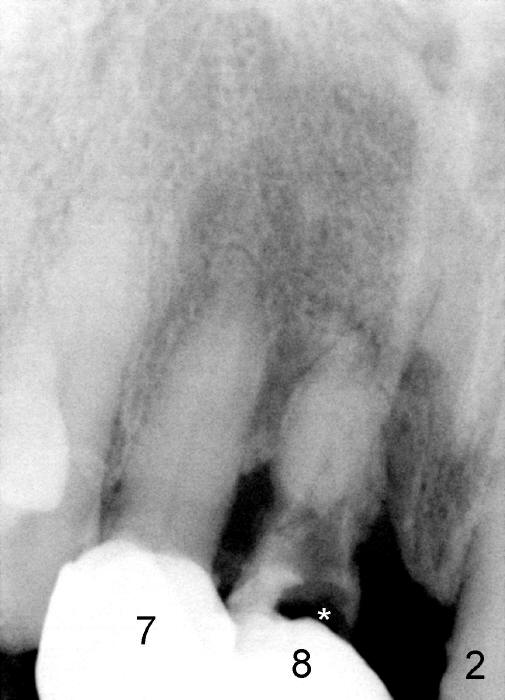

A 64-year-old lady requests replacing #7 and 8 crowns (Fig.1,2). When #8 is extracted, the labial plate is found to be missing (Fig.3). Following 2 mm pilot drill (Fig.4,5 P), 3.8 mm tap drill (Fig.6,7 T) and 4.5x14 mm implant (Fig.8 I) and 4.8 mm abutment (Fig.9 A), corticocancellous bone is harvested from the left tuberosity and placed in the labial gap of the socket (Fig.10 G). Collagen dressing is placed over the bone graft (Fig.11 C). The former is secured in place by an immediate provisional (P).

One year post cementation, there is cortical bone formation mesial to the implant (Fig.19 <). Buccal concavity is minimal (Fig.20).